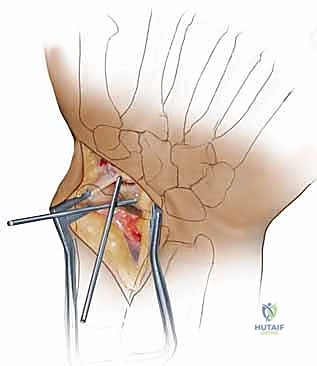

5. التثبيت الداخلي الدقيق (Internal Fixation)

بعد وضع الرقعة في مكانها الصحيح، يجب تثبيت كل شيء بقوة لضمان عدم تحرك العظم أثناء فترة الشفاء. يستخدم البروفيسور هطيف أحدث التقنيات العالمية في هذا المجال: مسامير الضغط المجوفة بدون رأس (Headless Cannulated Compression Screws).

يتم أولاً إدخال سلك توجيهي دقيق (K-wire) للتأكد من المحاذاة المثالية تحت جهاز الأشعة السينية المباشر (C-arm) في غرفة العمليات. ثم يتم تمرير المسمار فوق السلك. يتميز هذا المسمار بأنه يضغط شظايا العظم والرقعة معاً بقوة شديدة، وبما أنه "بدون رأس"، فإنه يُدفن بالكامل داخل العظم تحت الغضروف المفصلي، مما يمنع أي احتكاك أو ضرر لباقي عظام الرسغ. في بعض الحالات المعقدة، قد يتم استخدام أسلاك كيرشنر (K-wires) إضافية لزيادة الاستقرار.